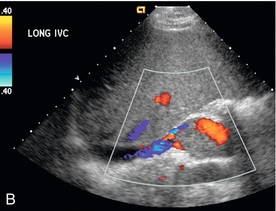

Диагноз РВТ основывается на обнаружении тромба, заполняющего почечную вену ( рис. 9-21 ), или неокклюзионного тромба, окруженного венозным потоком. В некоторых случаях вена может быть расширена тромбом. Отсутствие кровотока в почечной вене без признаков тромба может указывать на RVT; однако демонстрация низкого уровня цветового сигнала внутри вены при допплерографии не исключает возможности неокклюзионного или окклюзионного тромба почечной вены. Монофазные венозные волны являются аномальными, но не специфичными для RVT. Из-за возможности распространения тромба краниально в пределах НПВ ( рис. 9-22 ) и влияния на клиническое лечение, НПВ следует визуализировать в рамках сонографического исследования при оценке РВТ.

РИСУНОК 9-22 Тромб почечной вены. На изображении правой почечной вены в оттенках серого виден линейный тромб (стрелка), распространяющийся в НПВ. У этого пациента тромб был подвижным во время сердечной пульсации, что вызывало беспокойство по поводу возможной последующей эмболии.